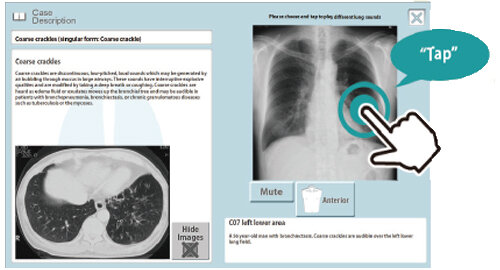

詳細な症例解説

- X線・CT画像を交えた症例解説で、それぞれの肺音の特長を視覚的にも学ぶことができます。

- X線画像上で、聴きたい部位をタップするとグループ学修用スピーカで音を出せます。